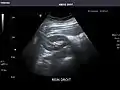

Spleen